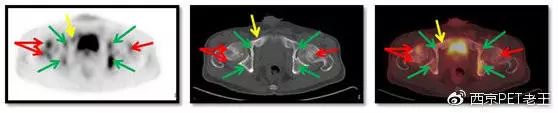

我们又发现了这么多的骨转移病变,那原发病灶究竟在哪里呢?我们仔细寻找,在左肺上叶发现了一个空洞样病变,边缘见细毛刺及胸膜牵拉征,呈葡萄糖代谢异常增高,我们考虑为恶性病变(肺癌?),如下图:

左肺上叶发现了一个空洞样病变(红色)